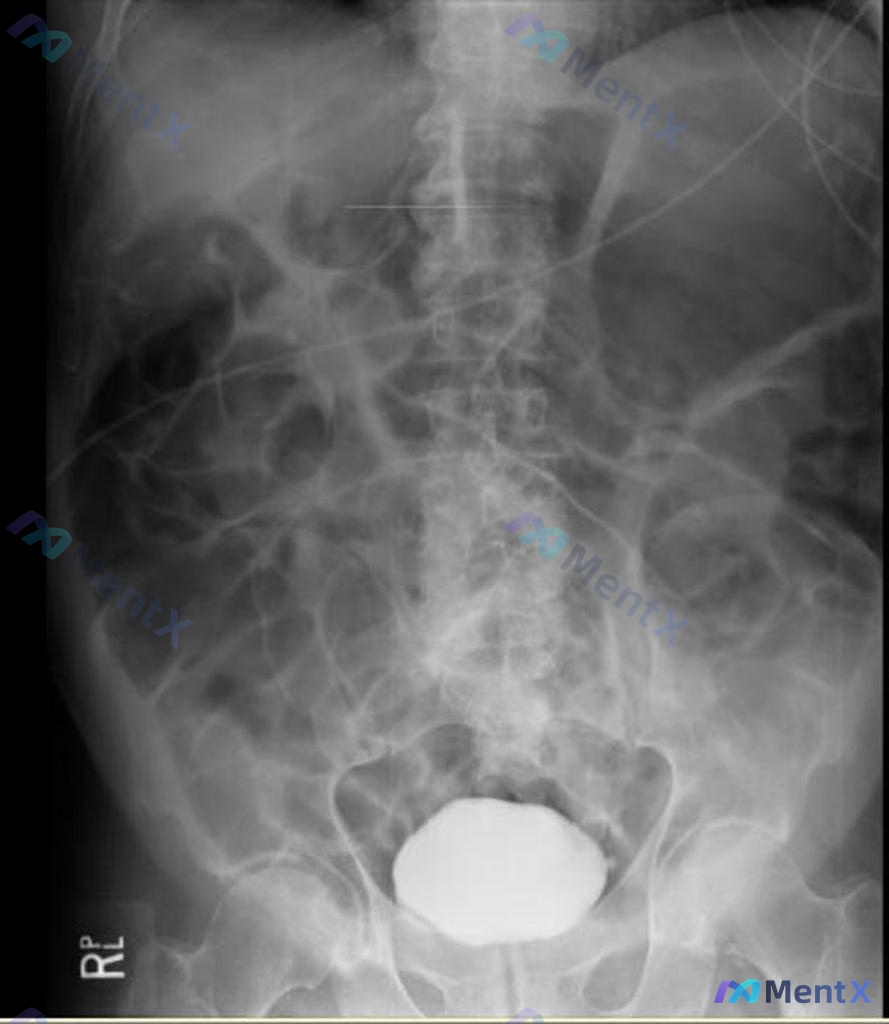

整理了一份关于“脾脏下极局灶性低密度影”的读片思路,感觉这里特别容易踩坑,分享出来和大家一起讨论。 先看影像核心事实 这份是上腹部CT平扫(软组织窗)的单张横断面图像: - 肝脏:轮廓、密度基本正常,未见明确占位 - 脾脏:大小形态正常,但下极靠近背侧边缘处可见一处局灶性低密度影,边界相对清晰,密度...